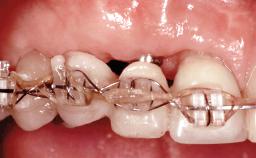

Replacement of Four Incisors with a Fixed Partial Denture on Two Narrow-Neck Implants after Implant Failure

| Placement Protocol | Early or late implant placement |

| Interim Prosthesis during Healing | Removable Removable |